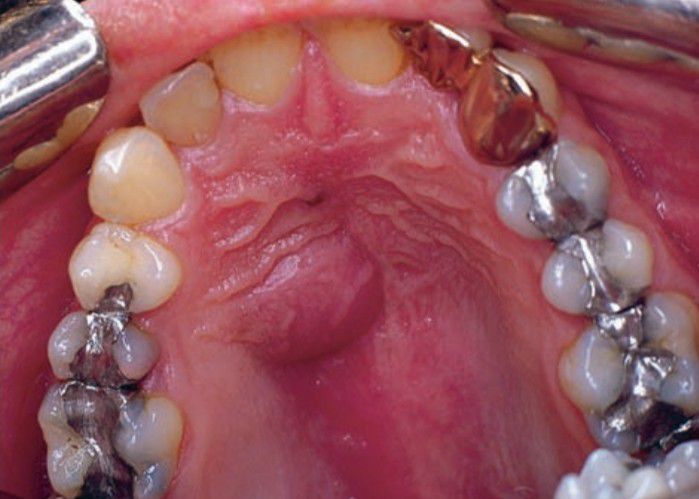

Palatal abscess

Palatal abscess representing extension of a periapical abscess.